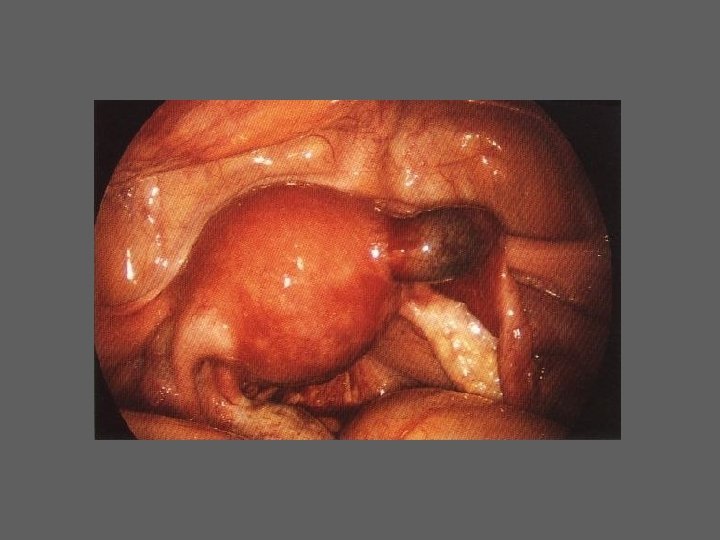

CELIOSCOPIA - INDICAÇÕES – Estudo e tratamento da infertilidade – Em todas as situações de sintomatologia obscura ou diversificada em que o exame ginecologico não revela uma patologia evidente: • Gravidez tubar • Doença inflamatória pélvica aguda • Algias pélvicas inespecíficas e crónicas – Realização de intervençõe cirurgicas

HISTEROSCOPIA DIAGNÓSTICA • Indicações /Importância (6 grupos) I. Esclarecimento de determinados sintomas ou de situações ginecológicas particulares II. Infertilidade III. Oncologia IV. Antecedentes de complicações Obstétricas específicas V. Esclarecimento de resultados “anormais” de outros meios de diagnóstico VI. Avaliação pré e pós-operatória da cirurgia histeroscópica

HISTEROSCOPIA - INDICAÇÕES Todas a situações em que se julgue vantajosa uma visualização completa da cavidade uterina, em particular: – Metrorragias – Dismenorreia adquirida – Infertilidade – Abortamentos de repetição e parto pré-termo – HSG anormal – DIU “perdido” – GIFT e ZIFT – Tratamento cirúrgico da patologia intracavitária: ● pólipos, miomas, septos, sinéquias, recessões endometriais ● baixos custos, reduzida morbilidade